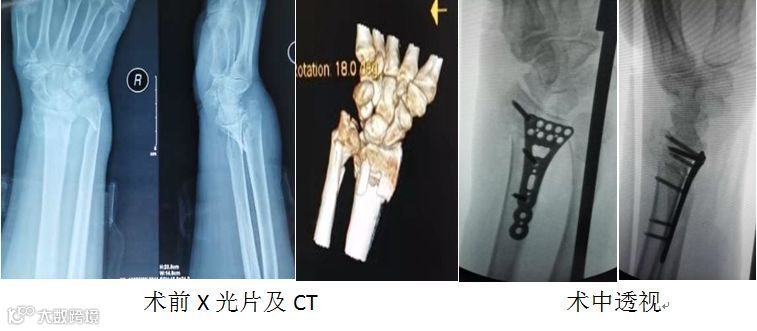

69岁女性患者,因“在家摔倒致右腕关节疼痛、活动受限2小时”入院。

诊断:右尺桡骨远端粉碎性骨折。

行右桡骨远端骨折切开复位内固定+植骨术,术后患者恢复良好。